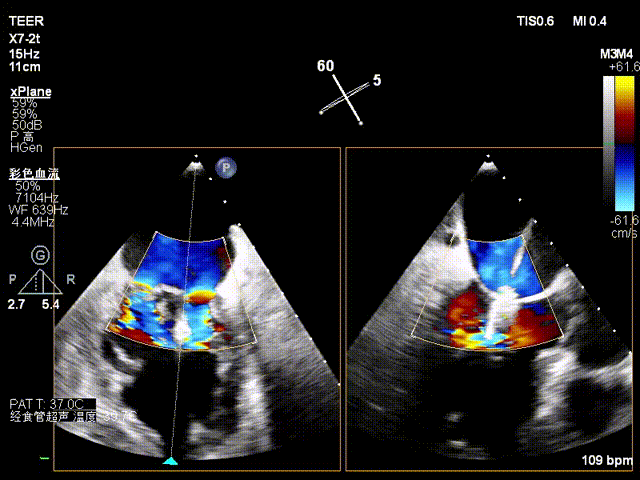

患者为73岁老年男性,经食道超声检查提示:急性二尖瓣腱索断裂合并反流,前叶长度:2.8cm,后叶长度:1.7cm,脱垂宽度:18mm,脱垂高度:8mm,瓣口面积:6.5cm²。

术前影像

X-plane2区彩色

3D彩色